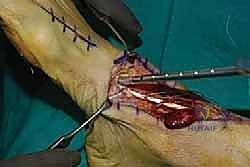

7. ماذا يحدث لإصبع القدم الكبير؟ (معالجة الجذع المتبقي)

بما أننا أخذنا الوتر الذي يرفع إصبع القدم الكبير، هل سيسقط الإصبع؟ لتجنب ذلك، يقوم الدكتور هطيف بإجراء تقنية تُسمى (Tenodesis). يتم خياطة الجذع المتبقي من وتر EHL في وتر العضلة الباسطة القصيرة للإصبع (EHB) أو في وتر الأصابع المجاورة (EDL). هذا يضمن بقاء إصبع القدم الكبير مرفوعاً ومستقراً ولا يعيق المشي.

8. الإغلاق والتجبير

يتم إغلاق الجرح على طبقات باستخدام خيوط تجميلية، ثم توضع القدم في جبيرة خلفية أو حذاء طبي (CAM Boot) مع إبقاء الكاحل في وضعية الانثناء الظهري (مرفوع للأعلى) لحماية الوتر المنقول من أي شد مبكر.